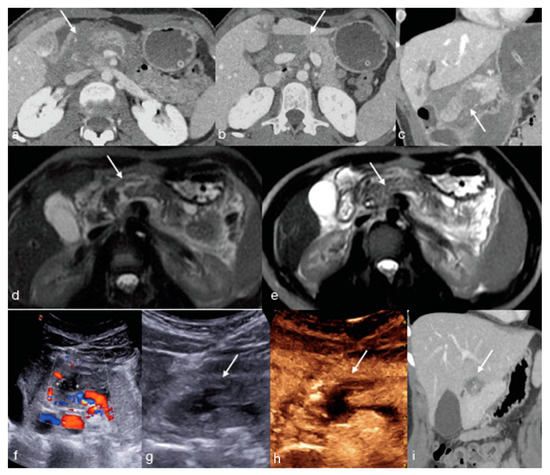

- Miele, V.; Piccolo, C.L.; Sessa, B.; Trinci, M.; Galluzzo, M. Comparison between MRI and CEUS in the follow-up of patients with blunt abdominal trauma managed conservatively. Radiol. Med. 2015, 121, 27–37. [Google Scholar] [CrossRef] [PubMed]